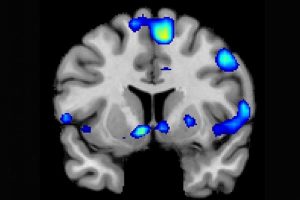

An fMRI scan shows regions of the brain that become active when devoutly religious study participants have a spiritual experience, including a reward center in the brain, the nucleus accumbens.

Powerful spiritual feelings were associated with activation in the nucleus accumbens, an area of the brain associated with reward, a new study reports.

Based on fMRI scans, the researchers found that powerful spiritual feelings were reproducibly associated with activation in the nucleus accumbens, a critical brain region for processing reward. Peak activity occurred about 1-3 seconds before participants pushed the button and was replicated in each of the four tasks. As participants were experiencing peak feelings, their hearts beat faster and their breathing deepened.

In addition to the brain’s reward circuits, the researchers found that spiritual feelings were associated with the medial prefrontal cortex, which is a complex brain region that is activated by tasks involving valuation, judgment and moral reasoning. Spiritual feelings also activated brain regions associated with focused attention.